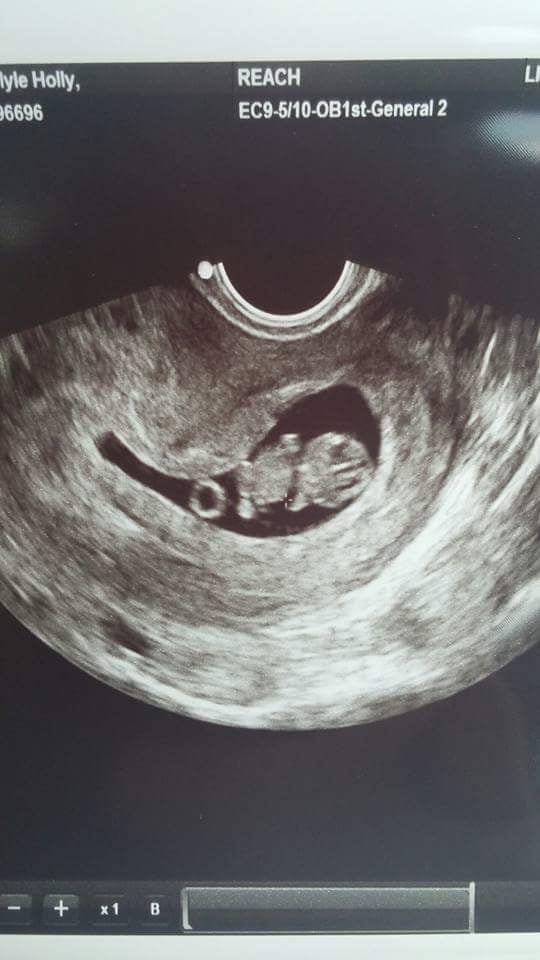

I had both levels of U/S - level II is a lot clearer and the machines are a LOT newer and have all these gadgets and buttons on them. There's definitely a difference in machines and picture quality. They're both 2D and black and white, but level II machines are a lot clearer/sharper and less fuzzier. Here's examples: Granted, these are 1st trimester ones but I don't have any pics in my phone from the 2nd trimester U/S.

Level II @ 9 weeks at RE's (where they use level II machines) and regular U/S @ OB at 10 weeks